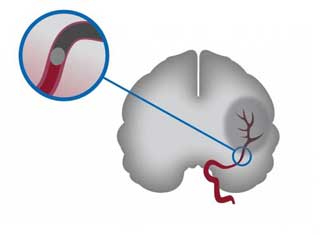

Тромб в кровеносном сосуде может перекрыть его просвет и вызвать некроз (гибель тканей) органа или его части, который получает кровоснабжение из этого сосуда. В артериях конечностей это может привести к гангрене, в сердце — к инфаркту, в мозге — к инсульту, а в легочной артерии — к острой легочно-сердечной недостаточности. В венах тромбы менее опасны, но могут вызвать тромбоэмболию, когда части тромба отрываются и распространяются с током крови в сердце и другие органы.

Как образуются тромбы в голове

- Наиболее распространенный процесс образования тромбов — атеротромбоз. Он начинается с нарушения липидного обмена, в результате чего в интиме сосуда откладывается холестерин, образуя атеросклеротическую бляшку. На начальном этапе она не проявляет себя. Постепенно увеличиваясь, бляшка сужает просвет сосуда, создавая завихрения крови. В какой-то момент она может надорвать стенку артерии, чаще всего при внезапном скачке давления. В место надрыва устремляются тромбоциты, формируя тромб.

Образовавшийся сгусток может перекрыть ток крови в месте своего расположения или оторваться и закупорить более мелкий сосуд.